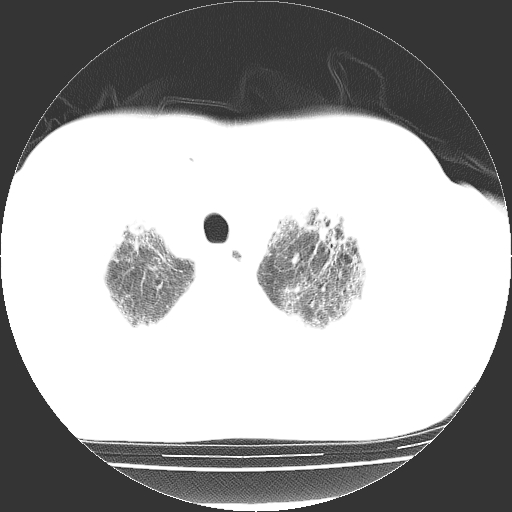

男,68岁,咳嗽、胸闷、发烧三天,查体:双肺散在湿罗音。

首先考虑特发型肺间质纤维化;两侧少量胸腔积液。

依据:1、两肺广泛条索状、网格状、蜂窝状改变。

1.双肺间质纤维化并感染;

2.双肺慢支炎肺气肿;

3.支扩并感染;

双肺多发条索状、网格状及小灶状密度增高影。考虑慢支合并感染.间质纤维化,双侧少量胸腔积液

两肺广泛条索状、网格状、蜂窝状改变。肺间质纤维化,肺心病,双侧胸腔积液